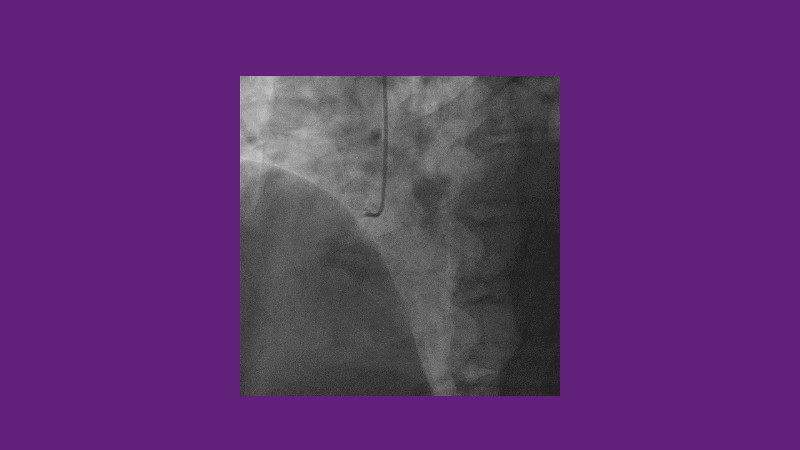

Leave nothing behind - Advancing DCB strategies in complex interventions

Explore cutting-edge strategies for optimizing drug-coated balloon (DCB) procedures in this session. Uncover practical tips to improve outcomes, review key indications, and examine international consensus on DCB use. Case presentations and expert discussions offer insights to refine your approach.